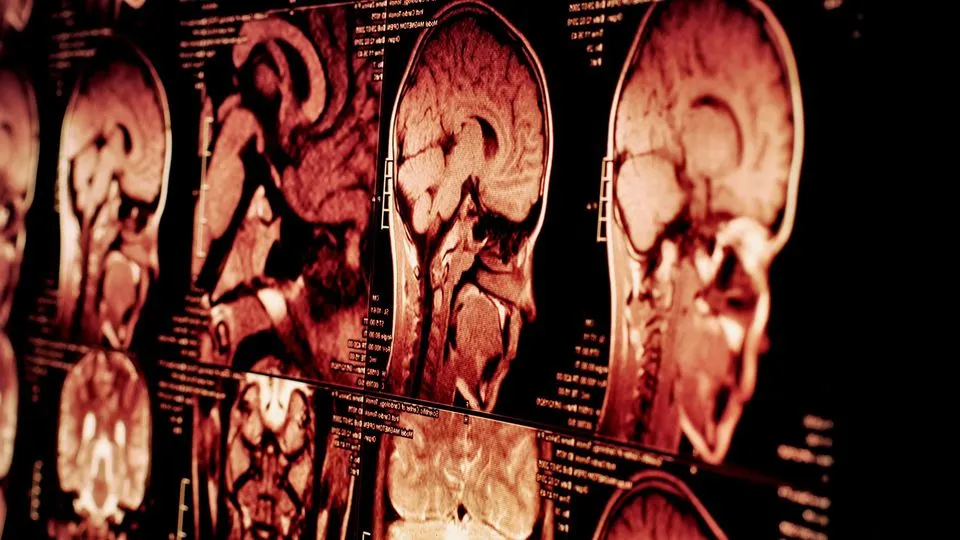

A groundbreaking study reveals glioblastoma, the deadliest brain cancer, erodes the skull to manipulate the body's immune system, changing how scientists view the disease.

Scientists have made a startling discovery about glioblastoma, the most aggressive form of brain cancer. Research from the Montefiore Einstein Comprehensive Cancer Center reveals the tumor actively erodes the skull and hijacks the body's immune system.

This finding challenges the long-held view of glioblastoma as a disease confined to the brain. Instead, it is now being understood as a systemic condition that wages a two-front war: one in the brain and another within the skull's own bone marrow.